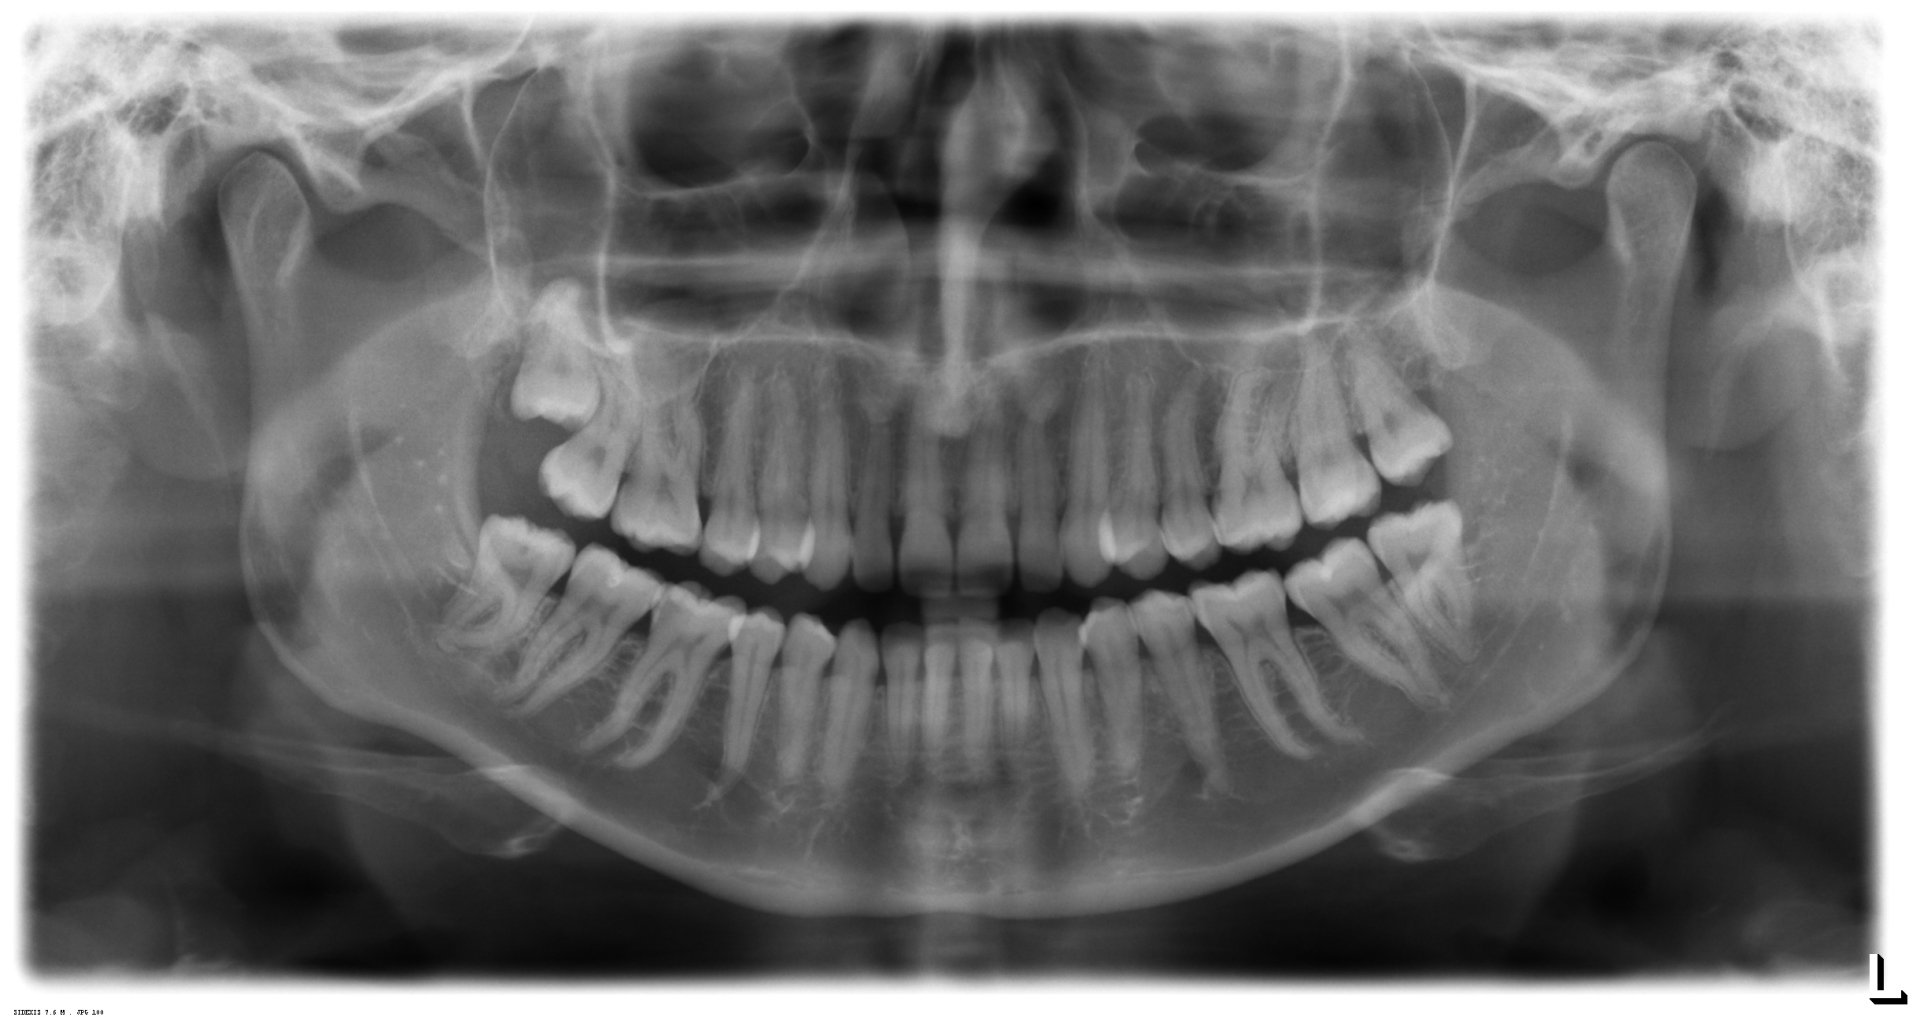

¿Cuándo se deben extraer las muelas del juicio?

quistes

Quistes odontogénicos, tumores

inflamación recurrente

Riesgo: Inflamación potencialmente mortal

Caries (también en el diente de enfrente)

La caries dental en las muelas del juicio puede ser difícil y no fácil de tratar a largo plazo

Antes de la disgnatia

La osteotomía conduce a través de la región de la muela del juicio.